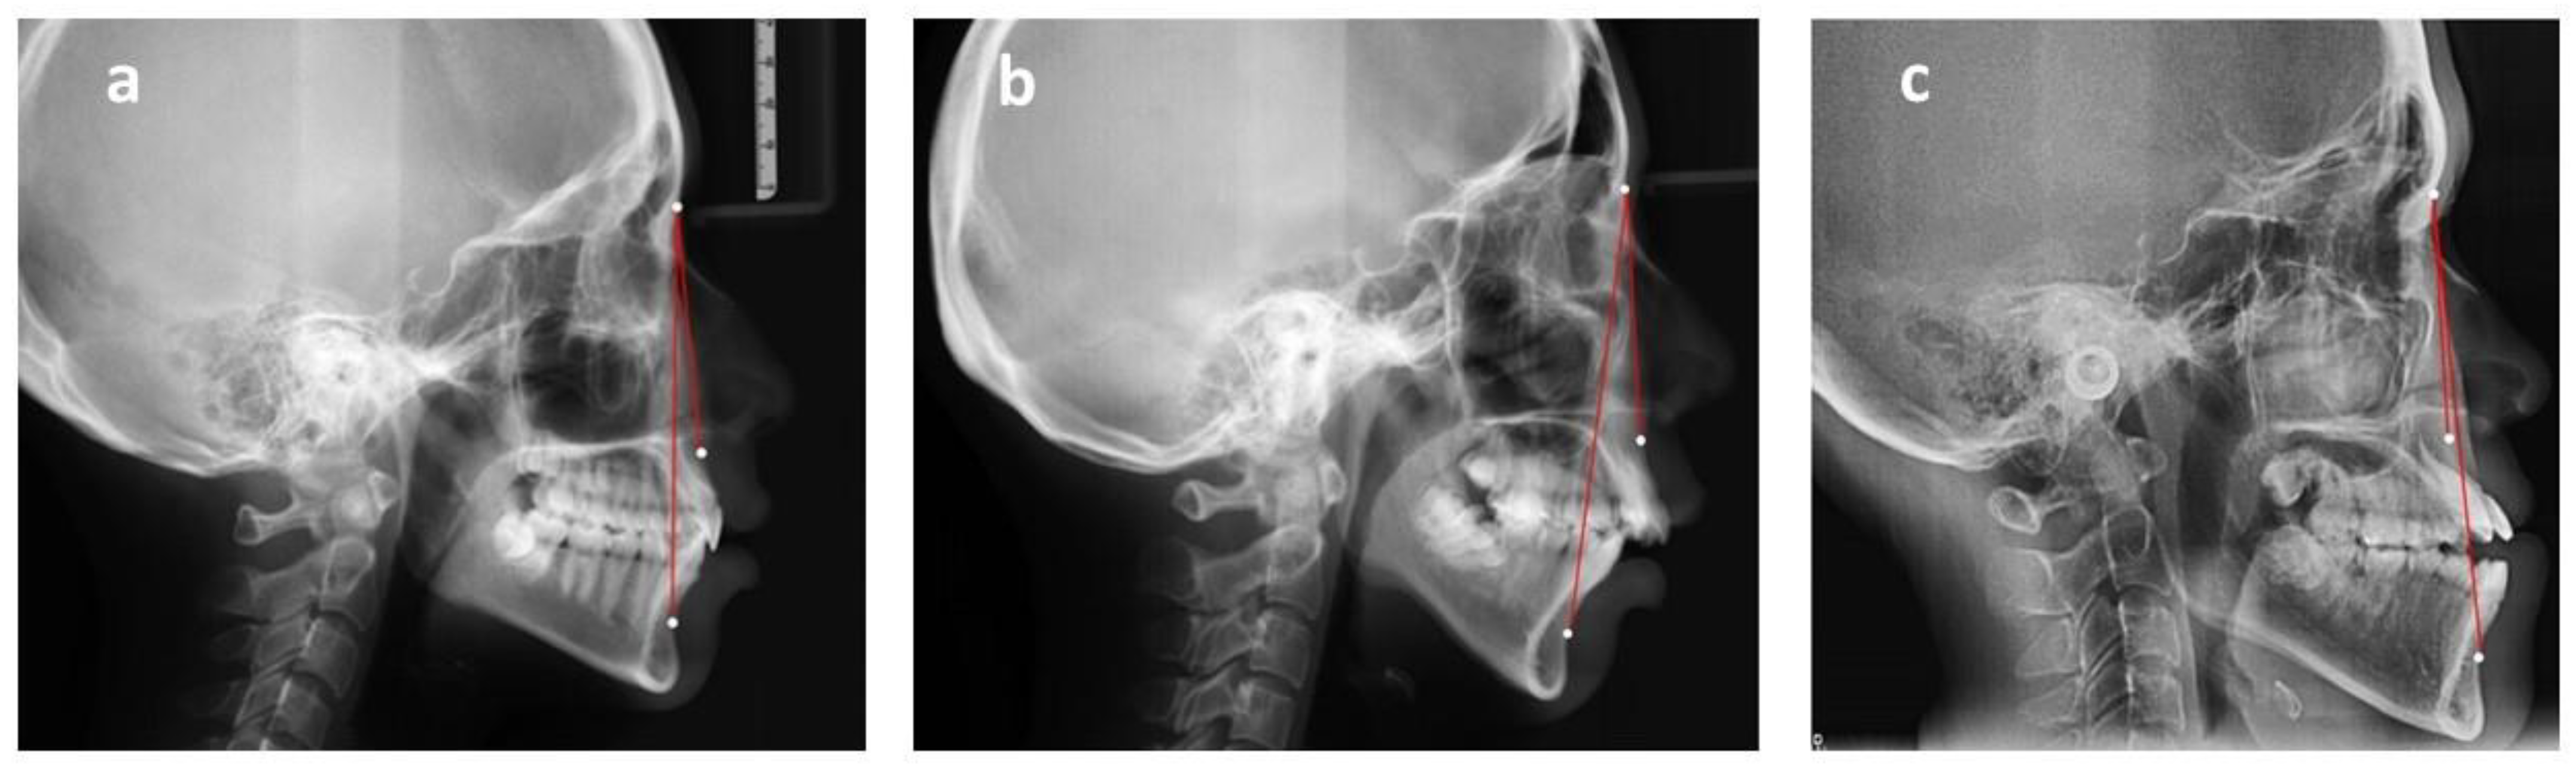

The skeletal relationship between the maxilla and mandible of orthodontic patients was categorized as Class I, Class II, or Class III [35,36,37,38] (Figure 1 and Figure 2). Steiner’s analysis [39] and Tweed analysis [40] were used for the measurements according to the analysis of St. Louis University in the United States, where the first author was trained for her orthodontic graduate program. The dental relationship between the maxilla and mandible of orthodontic patients was defined as molar Class I, Class II, or Class III (Figure 3). The DMFS index was expressed as the total number of teeth that were decayed (D), missing (M), or filled (F) in an individual with permanent dentition. There were five surfaces (facial, lingual, mesial, distal, and occlusal) for the posterior teeth and four surfaces (facial, lingual, mesial, and distal) for the anterior teeth when the DMFS index was calculated.

Figure 2. Sagittal skeletal classification based on ANB angle. ANB: The angle is constructed by connecting the A point, nasion, and B point. According to the Steiner analysis, the measurement represents the skeletal relationship between the maxilla and mandible. (a) Class I relationship: ANB is between 2 and 4. (b) Class II relationship: ANB is greater than 4. (c) Class III relationship: ANB is below 2 or negative.